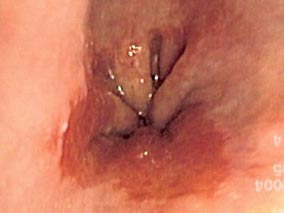

Une étude récente vient apporter des arguments aux tenants de la surveillance systématique. Il s’agit d’une étude prospective de cohorte, incluant 720 patients présentant un œsophage de Barrett d’au moins 2 cm confirmé par la présence de métaplasie intestinale. Les patients ont été surveillés pendant 6,6 ans en moyenne, selon les recommandations de l’American College of Gastroenterology.

Une progression néoplasique est dépistée chez 50 (7 %) d’entre eux, après environ 3,2 ans (2,0 -5,3). Pour 39 patients (78 %), l’endoscopie de contrôle découvre une dysplasie de haut grade ou un carcinome in situ ; pour 7 (14 %), il s’agit d’une tumeur T1 ; pour 2 (4 %), d’une tumeur T2, et pour 2 autres, d’une tumeur T3. L’incidence totale des lésions de haut grade et des adénocarcinomes s’élève ainsi à 1,3 pour 100 patients-années.

Neuf (18 %) des patients chez qui l’endoscopie de contrôle a dépisté une progression néoplasique bénéficieront d’une surveillance intensive par endoscopie, 30 (60 %) d’un traitement endoscopique, 4 (8 %) d’une résection chirurgicale et 2 (4 %) d’une résection chirurgicale avec chimiothérapie néoadjuvante. Au moment de la communication des résultats de l’étude, 4 patients venaient d’être diagnostiqués et n’avaient pas encore reçu de traitement et 1 patient était décédé pour un motif autre que son œsophage de Barrett.

Pour les auteurs, ce constat est en faveur d’une surveillance systématique qui permet de détecter des lésions de haut grade ou des adénocarcinomes à un stade précoce et encore accessible au traitement endoscopique. Ils s’appuient sur les taux de survie constatés dans cette étude : la survie globale à 5 ans de 78 % (intervalle de confiance à 95 % [IC95] de 0,61 à 0,94) et le taux de survie spécifique à 5 ans de 91 % (IC95 de 0,81 à 1,00), ce qui selon les auteurs est le maximum de ce qui est attendu classiquement pour ce type de patients (stade 0, TisN0M0, survie à 5 ans > 90 %).